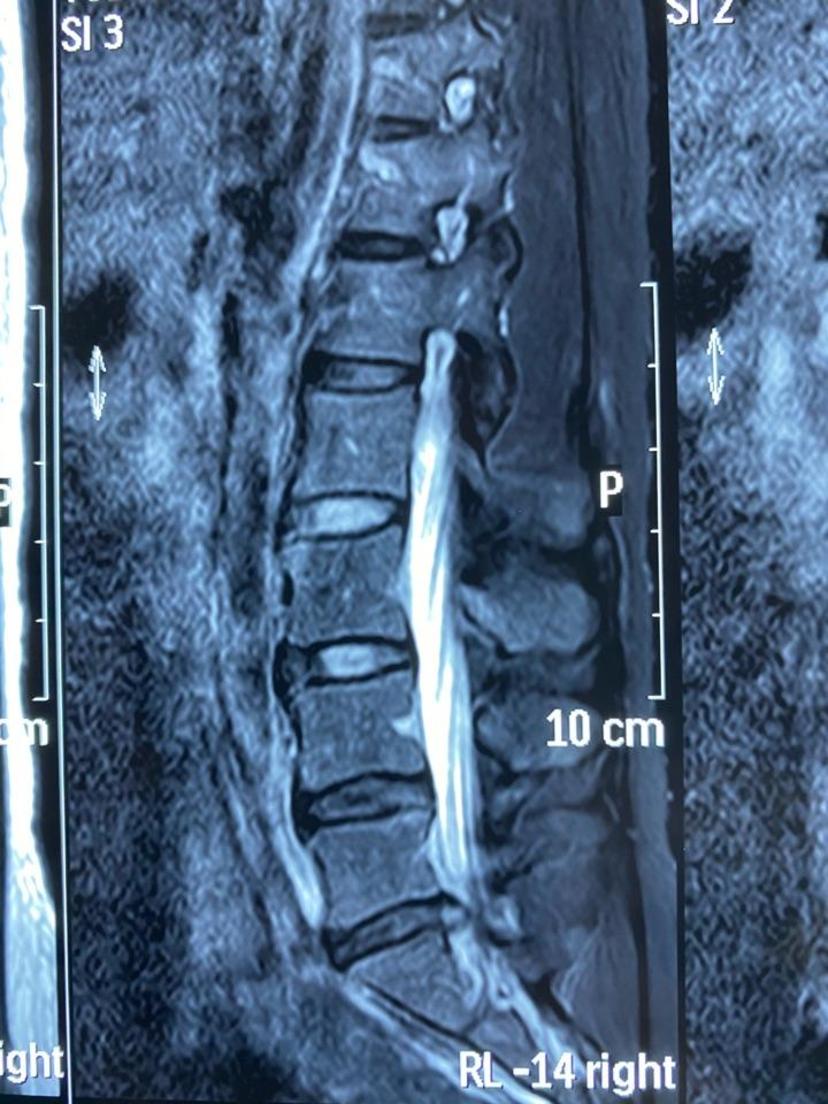

磁共振显示巨大突出的椎间盘压迫硬膜囊

磁共振平扫显示左侧神经根严重受压